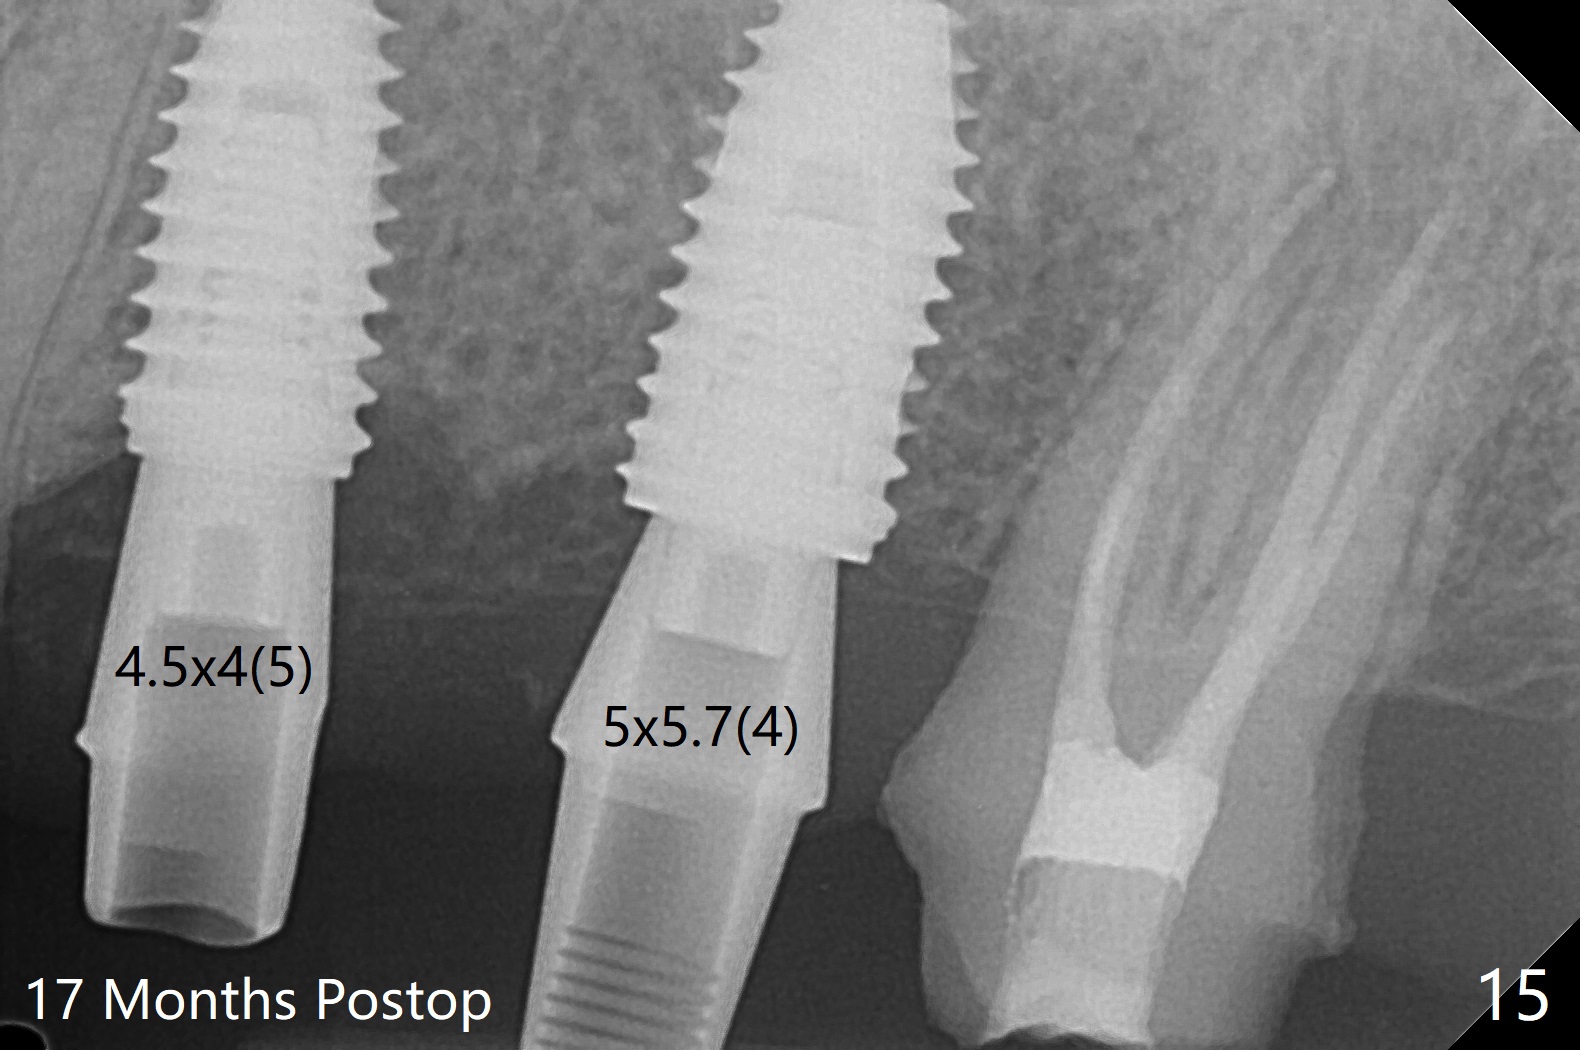

After extraction of the tooth #13 residual root, the bone in the distal wall of the socket looks white. Intraop PA rules out root structure (Fig.1 *). Osteotomy is conducted according to drill sequence. Bitewings are taken to check implant placement level (Fig.2,3). Following implant level adjustment and healing abutment installment (Fig.4,5 (*: bone graft)), the implant at #13 is found to be close the root of #12 (Fig.6 *), i.e., not parallel to the implant at #14. Introspectively, 2.2x10 mm drill seems to be long. When it touches the bone, the cylinder portion of the drill (Fig.7 red) does not engage into the sleeve (green). When it goes into the bone, it may have been deflected mesial due to the slope of the distal wall of the socket (hard bone, Fig.8 open arrow)). If a shorter drill (such as 2.2x7.3 or 8.5 mm) were used (Fig.9), the deflection would be minimal if drilling is slow (Fig.10). CT taken 1 week postop shows that the implant at #13 is approximately 1 mm near the root of the tooth #12, but the neurovascular bundle to the latter seems not to have been interrupted (Fig.11,12). The buccopalatal trajectory at #14 is within normal limit (Fig.11,13 (B: buccal)). There is no periapical radiolucency at #12 five months postop (Fig.14). However the cemented abutments are incompletely seated (<). The patient is reluctant to return for impression 17 months postop (due to coronavirus); with attention, the same abutment at #13 is reseated completely; an abutment with longer cuff and narrower diameter is also seated completely (Fig.15).